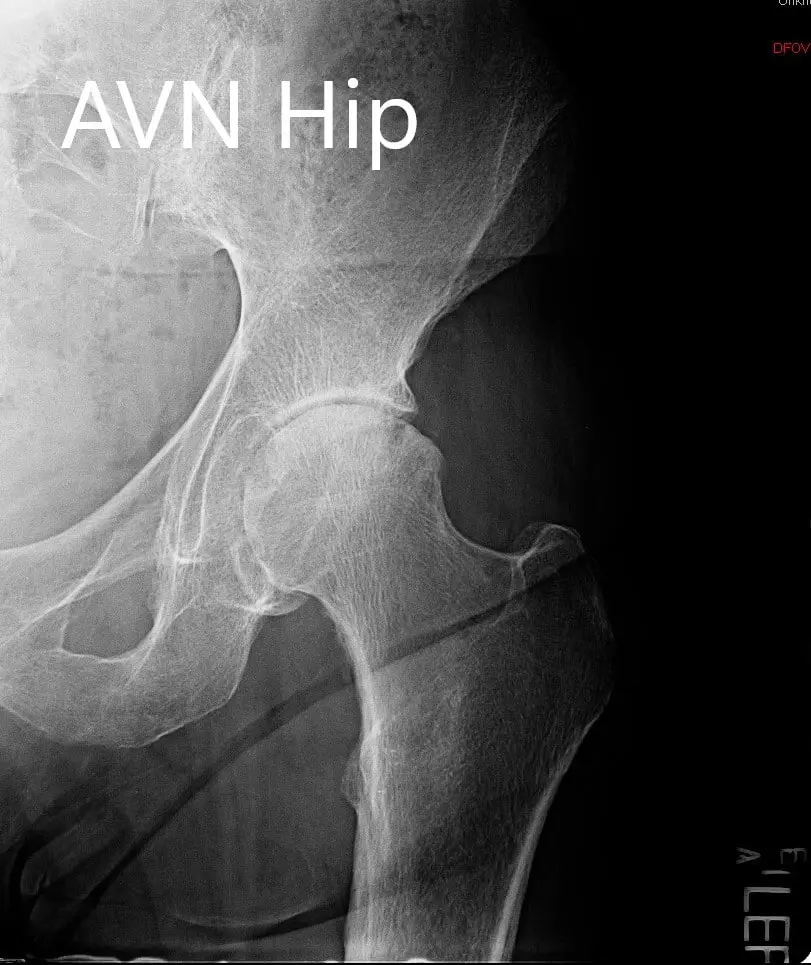

Las imágenes revelaron una osteoartritis severa en la cadera izquierda y una resonancia magnética sugirió cambios en necrosis avascular en la cadera izquierda. En vista del dolor de cadera que limita el estilo de vida y las comorbilidades de los pacientes, se recomendó un reemplazo total robótico de cadera. Se discutieron extensamente con el paciente los riesgos, beneficios y alternativas. Él estuvo de acuerdo con el plan. También se realizó una tomografía computarizada preoperatoria.

Radiografía preoperatoria que muestra la AP y las vistas laterales de la cadera izquierda

DIAGNÓSTICO(S) PREOPERATORIO(S): Artritis en la cadera izquierda secundaria a necrosis avascular.